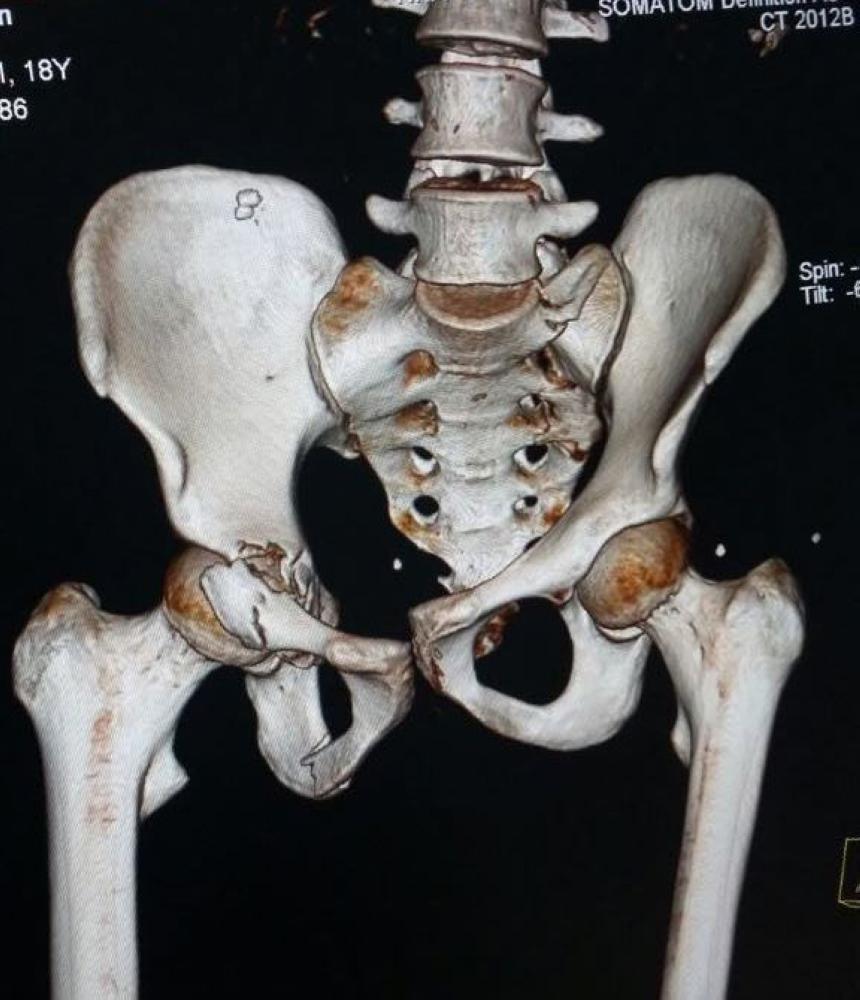

وقالت صحة الجوف: «المصاب تعرض لحادثة مرورية نتج عنها كسر بجسم الفقرة العنقية السادسة، وكدمات بالرئة اليمنى، وكسر بالجدار الأمامي المكون لعظمة مفصل الفخذ، وتوسع بعظام العانة، وخلع خلفي بالمفصل الأيمن، وبعد عرض الحالة على فريق طبي بالمستشفى قرر إجراء تدخل جراحي لرد الخلع المفصلي، وتوسع عظام العانة، وتثبيت الكسور بواسطة شرائح ومسامير معدنية خاصة لمثل هذه الكسور».